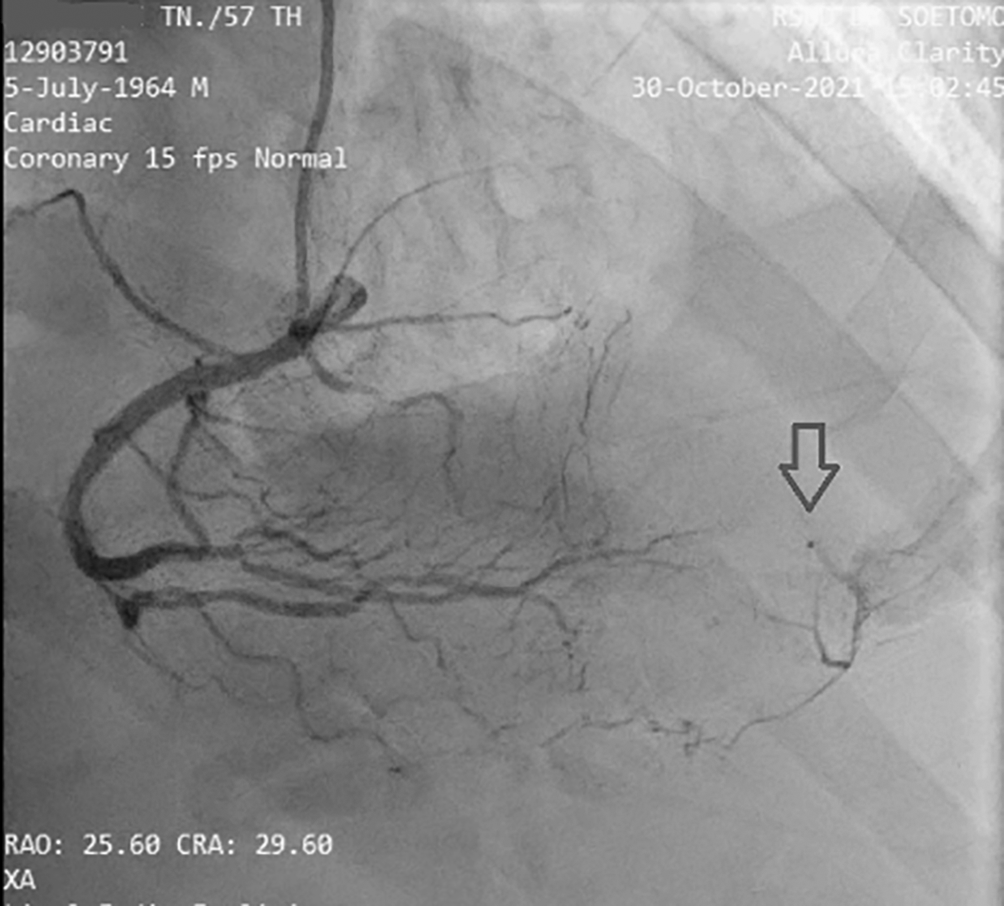

Before the invasive strategy was done, the patient had another electrocardiography eight hours after the first electrocardiogram, based on the second (Figure 2). The electrocardiogram showed ST-segment elevation changes that were greater than 1 mm. The early invasive strategy (Figure 3 and Figure 4; Extended data: Video 1 and Video 2)3,4 showed that the left anterior descending artery (LAD) had a critical occlusion of 99% in the middle of left anterior descendants coronary artery (Figure 3). The left circumflex artery (LCx) had non-significant stenosis of 40% proximal and 65% distal, and right coronary artery (RCA) had non-significant stenosis of 55% distal. The RCA had grade 2 collateral arteries that supply blood to the middle of left anterior descendants coronary artery (Figure 4).

The cardiac catheterization results found that a collateral artery originating from the right coronary artery (RCA) supplied the mid-distal left anterior descendants (LAD) coronary artery. Therefore the heart muscle that should have been severely damaged due to not getting blood supply from the LAD could still survive due to the presence of the collateral artery. Previous data has established that enough collaterals can prevent ischemia and directly induce spontaneous reperfusion in one-third of NSTE-ACS patients. Spontaneous reperfusion with well-developed coronary collateral circulation is associated with a better prognosis in cardiovascular mortality reduction.18